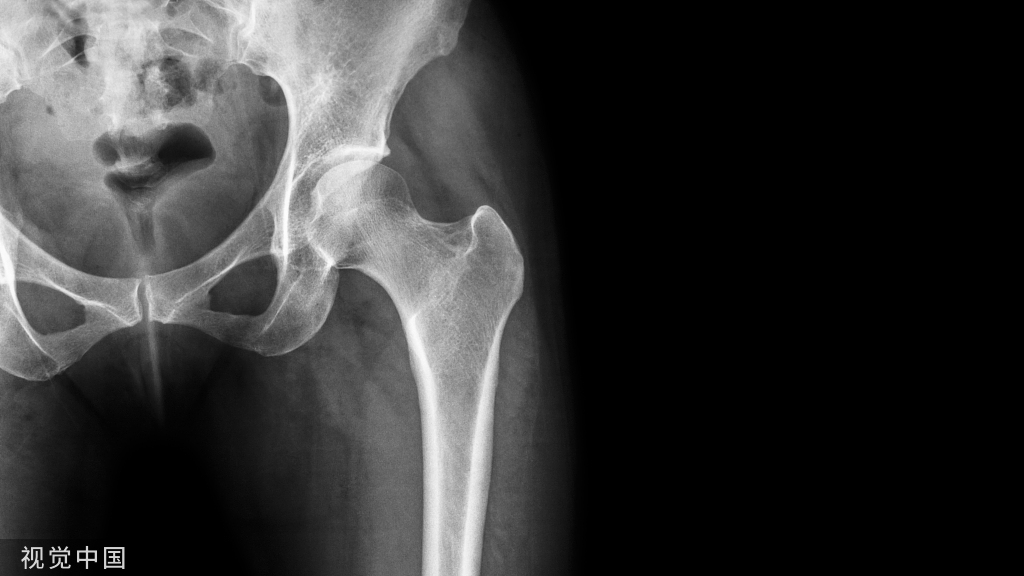

X线是诊断桡骨远端骨折最常用的成像方式。一般来说,腕关节正、侧位X线片即可明确诊断,如有必要,可加拍其他体位(如腕关节斜位)。X线检查能评估桡骨高度、掌倾角、尺偏角、尺骨茎突骨折和DRUJ的匹配程度等。双侧X线片对比阅片对诊断也有一定价值。